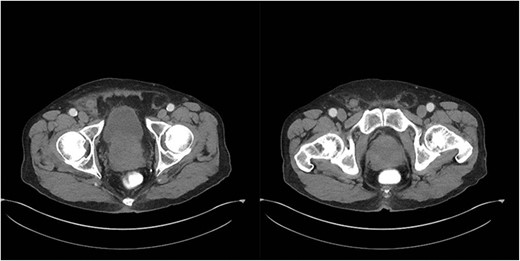

An 81-year-old male with a past medical history of childhood repair of cardiac septal defect presented to our emergency department (ED) with a two-day history of vague abdominal pain that migrated to his right groin with an associated non-reducible right groin mass. The non-reducible groin mass persisted, and his pain progressed that prompted him to come to the ED. Clinical examination revealed a firm, tender and irreducible right inguinal mass. The remaining clinical and laboratory tests were normal. Contrast-enhanced computed tomography (CT) of the abdomen and pelvis was performed. CT presented an acute appendicitis within a right inguinal hernia and a dilated appendix, measuring 13 mm in diameter and demonstrated periappendiceal fat stranding with no evidence of rupture (Figs 1–3). Patients’ history, physical exam and imaging findings were consistent with the preoperative diagnosis of an Amyand’s hernia with acute appendicitis. It was determined the patient will require operative intervention.

Sagittal CT abdomen with oral contrast showing a dilated appendix periappendiceal fat stranding within a right inguinal hernia and no evidence of rupture.